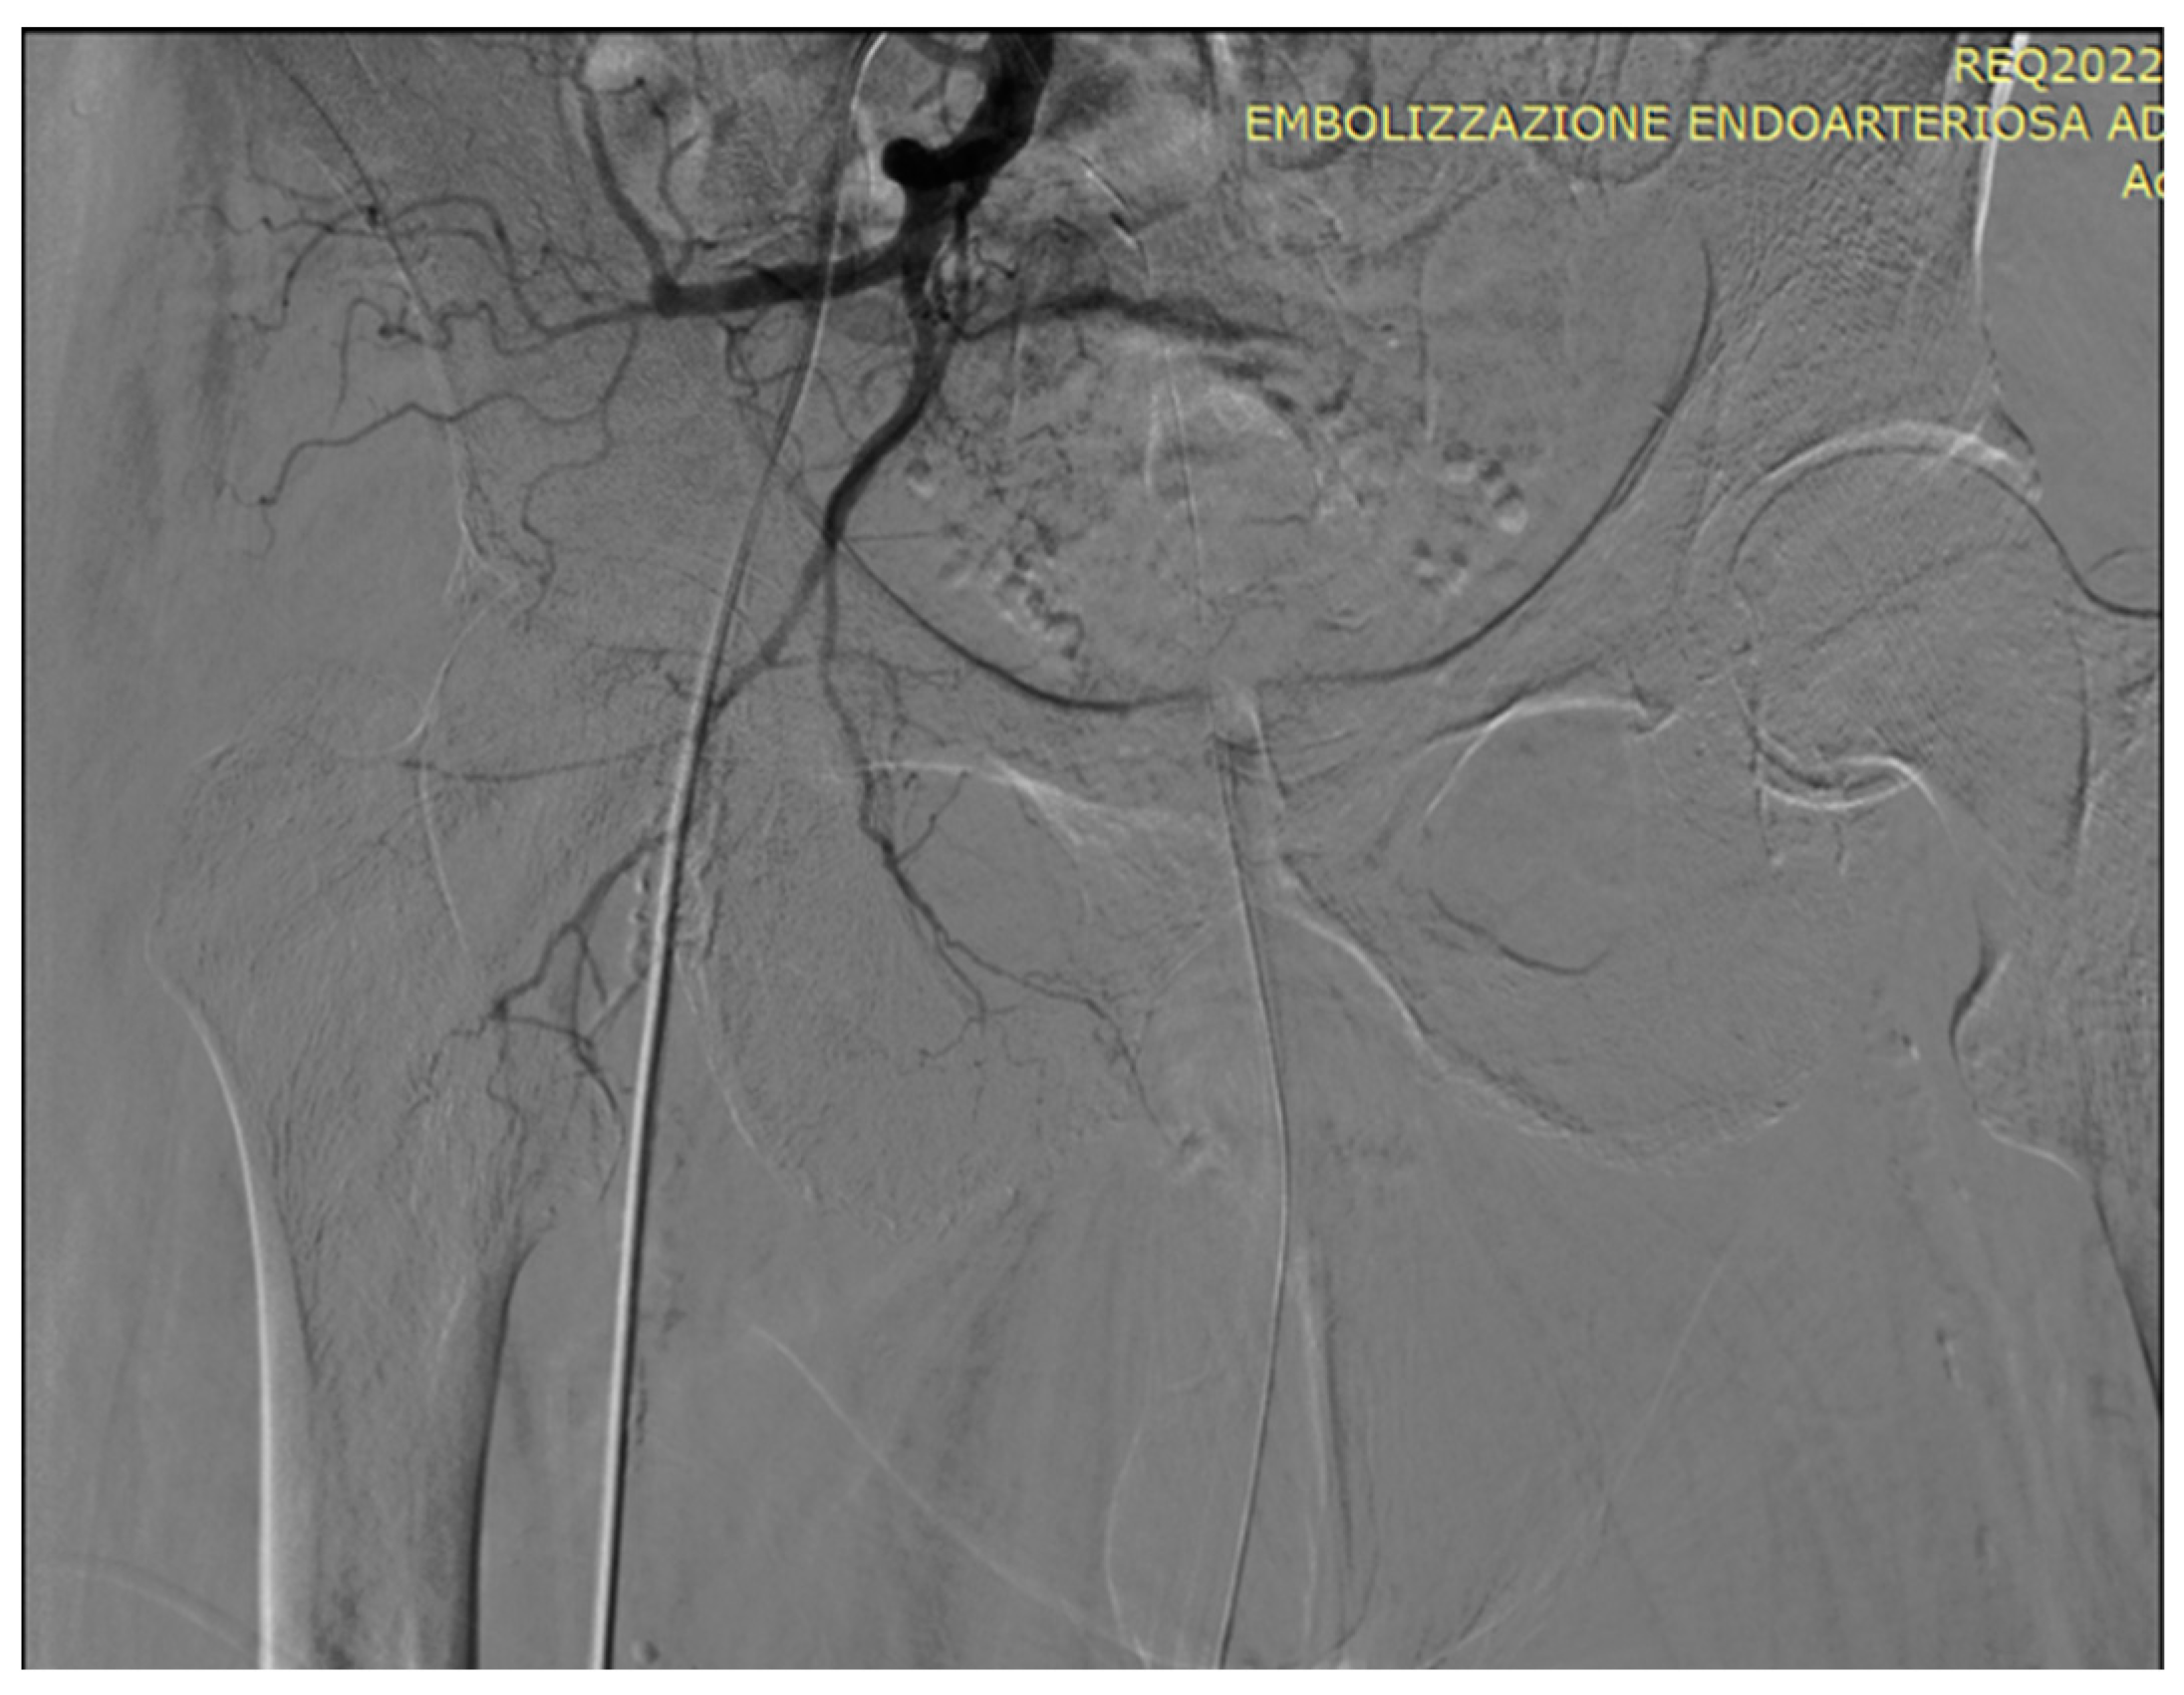

5. A suggested algorithm and a demonstrative patient profile

5.1. Technical details of PAE